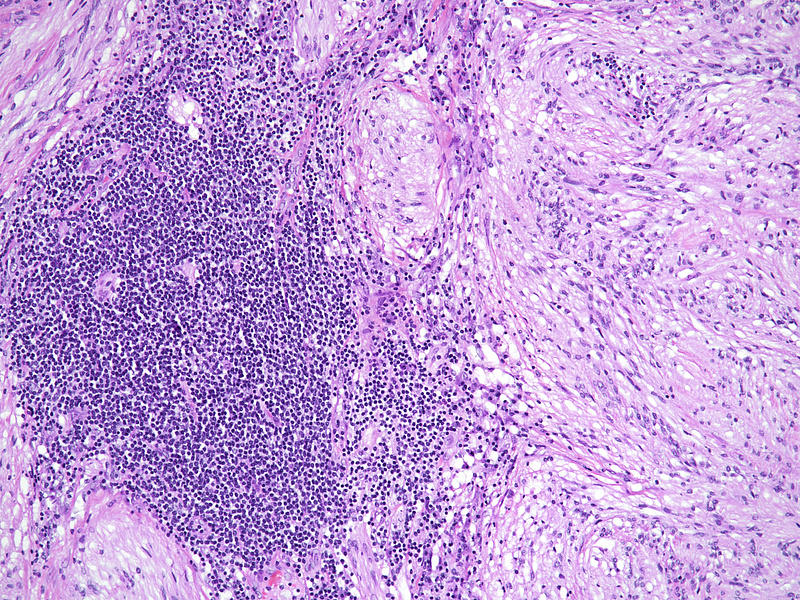

During laparoscopic surgery, the tumour proved to be confined to the appendix, with no other intra-abdominal findings (Panel A). The resection specimen disclosed a well circumscribed solid tumour, 4.2 cm in maximum diameter, with a homogeneously yellowish-white cut surface (Panels B and C).  Histologically, we observed a loose to densely cellular, spindled-cell neoplasia, arranged in fascicular and sweeping patterns (Panel D). Lymphoid aggregates, sometimes forming lymphoid follicles with germinal centres, were  found distributed at the periphery and also throughout the tumour (Panels E and F). The neoplastic cells had sparse cytoplasm and elongated, bland nuclei with inconspicuous nucleoli; focal and moderate atypia was noted (Panel G). Mitotic activity was <5mitoses/10HPF. Haemorrhage or necrosis were not observed. Upon immunohistochemistry, there was diffuse and strong positivity for S100 protein (Panel H) and moderate positivity for GFAP (Panel I). CD117 marked intralesional mast cells, whereas the tumour cells were negative (Panel J). Desmin and smooth muscle actin were negative (not shown).

The characteristic morphology directs to the correct diagnosis: a well-circumscribed lesion, with a marbled appearance due to densely cellular areas alternating with densely cellular areas; and neoplastic spindled cells, sometimes with focal, degenerative atypia. Lymphoid cuffs, usually present in soft tissue schwannomas, have an unclear aetiology; in the appendix, its presence probably is due to remnants of local MALT-tissue. Long fascicular pattern, an epithelioid appearance, tumoral necrosis and increased mitotic activity must raise concern for malignant transformation to MPNST.